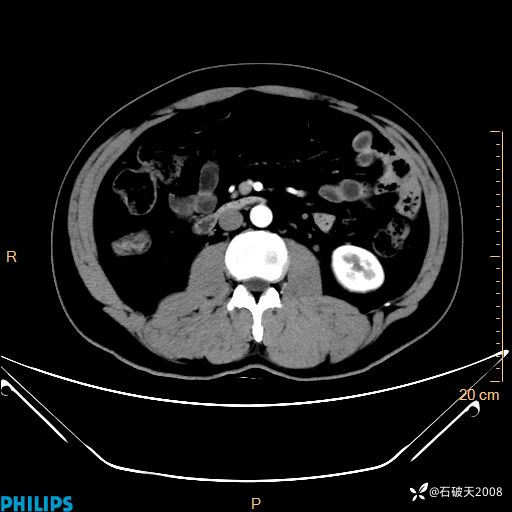

增强轴位